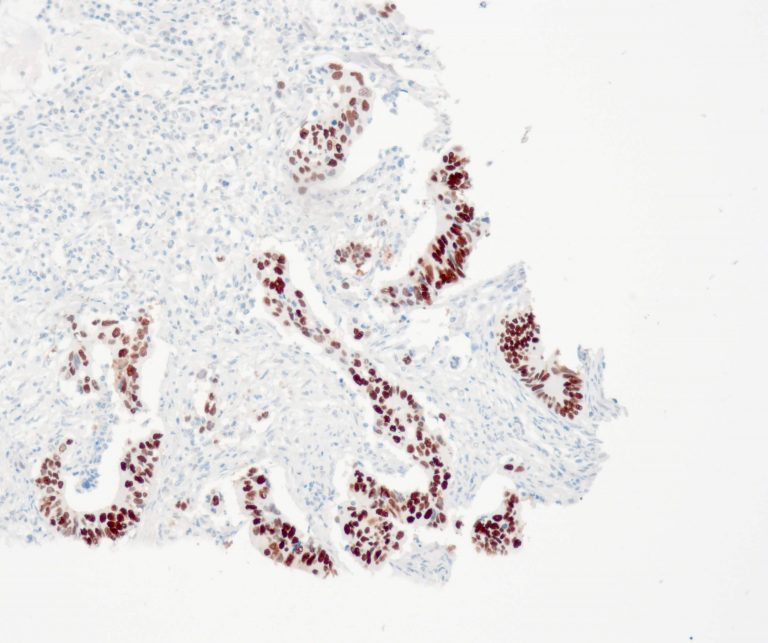

Vascular Pathology

Gastrointestinal (GI) Pathology

General Marker

Breast Pathology

Endocrine Pathology

Gynecological Pathology

Neuropathology

Infection Markers

Lung Pathology

Urinary Tract Pathology

Transplantation Pathology

Soft Tissue Pathology

Hematopathology